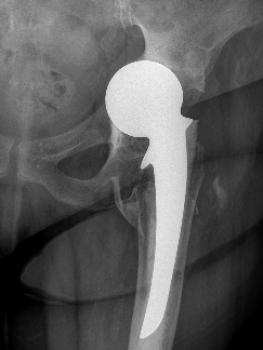

Clinical cases: variations of Exeter stem size and offset copes with almost all abnormal anatomies.

Figure 7 & Figure 8: DDH case with bowed femur and over-riding GT.